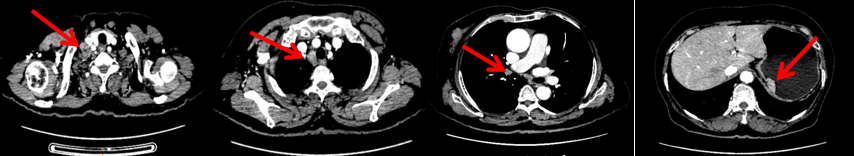

颈胸腹盆腔CT

右乳外上象限占位,考虑乳腺癌;右侧锁骨上、上纵隔及右肺门多发淋巴结转移(较大者24*15mm)。胃贲门处小弯侧胃壁明显增厚(26*12mm),考虑胃癌可能,周围脂肪间隙清;颈部未见明确异常。头颅MR未见脑转移。

2023.6.26复查PET-CT

1.右乳外上象限乳腺癌病灶(22*16mm),对比2023-04-14 CT(26*24mm)较前缩小,FDG代谢活跃。右侧腋窝小淋巴结(5mm),较前稍缩小,代谢不活跃。右侧锁骨上区、上纵隔淋巴结转移瘤(24*18mm),现大小同前相仿,代谢活跃(SUV:6.7)。

2.现胃贲门部术后改变,术区未见明显异常活性灶。

3.左乳、左侧胶窝术后改变,未见明显异常活性灶。双肺小结节。考虑炎性结节可能,建议复查;双肺门及纵隔另反应性淋巴结。

患者已接受胃癌根治术,术后通过PET-CT对病灶情况进行了评估。目前患者采用哌柏西利联合氟维司群方案治疗,乳腺病灶已明显缩小,但锁骨上淋巴结、纵隔及肺门淋巴结未见缩小。为进一步为患者制定更精准的治疗方案,龚畅教授与曾银朵教授组织了第二次多学科联合会诊。